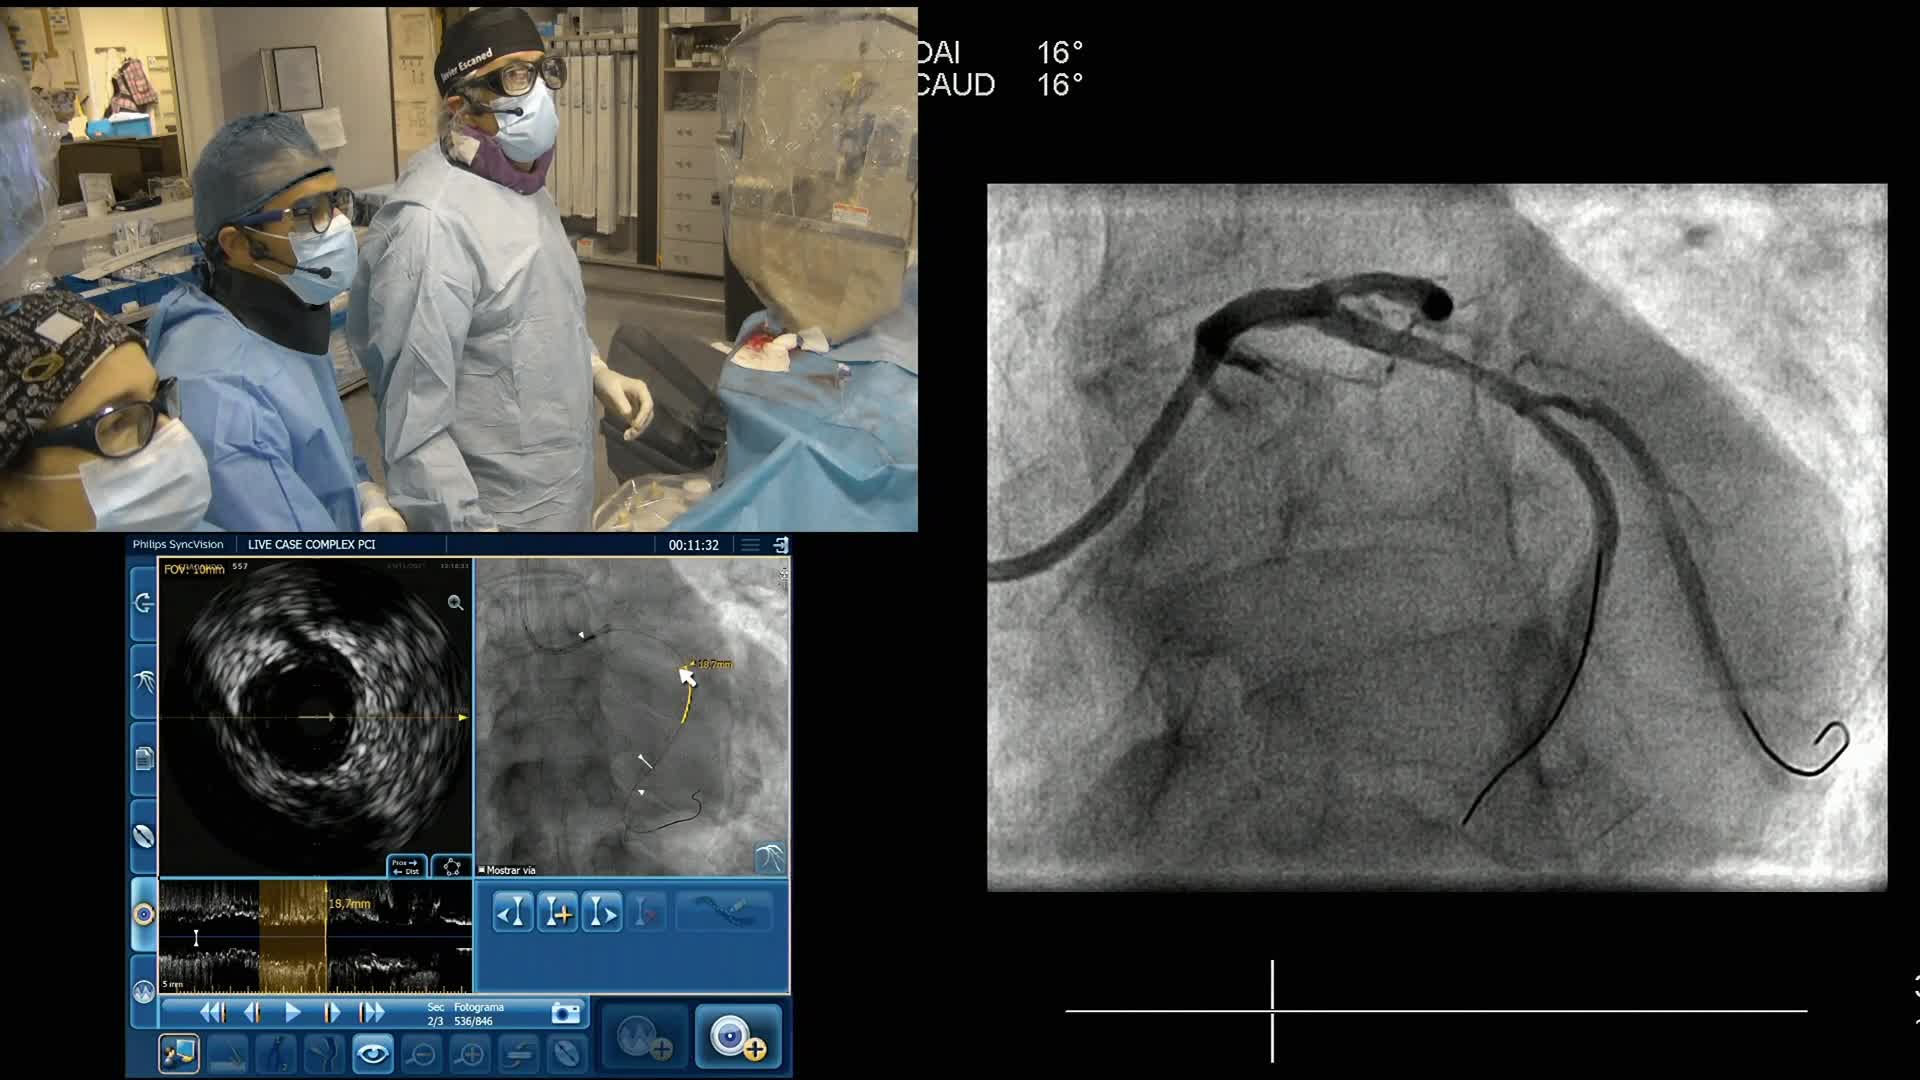

Advances in Co-registration, Coronary Physiology & Intra Coronary Imaging - April 2024 Day One

Advances in Co-registration, Coronary Physiology & Intra Coronary Imaging - April 2024 Day Two

Advances in Co-registration, Coronary Physiology & Intra Coronary Imaging - November 2023 Day One

Advances in Co-registration, Coronary Physiology & Intra Coronary Imaging - November 2023 Day Two

Advances in Co-registration, Coronary Physiology & Intra Coronary Imaging - November 2022 Day One

Advances in Co-registration, Coronary Physiology & Intra Coronary Imaging - November 2022 Day Two

Advances in Co-registration, Coronary Physiology & Intra Coronary Imaging - March 2022 Day One

Advances in Co-registration, Coronary Physiology & Intra Coronary Imaging - March 2022 Day Two